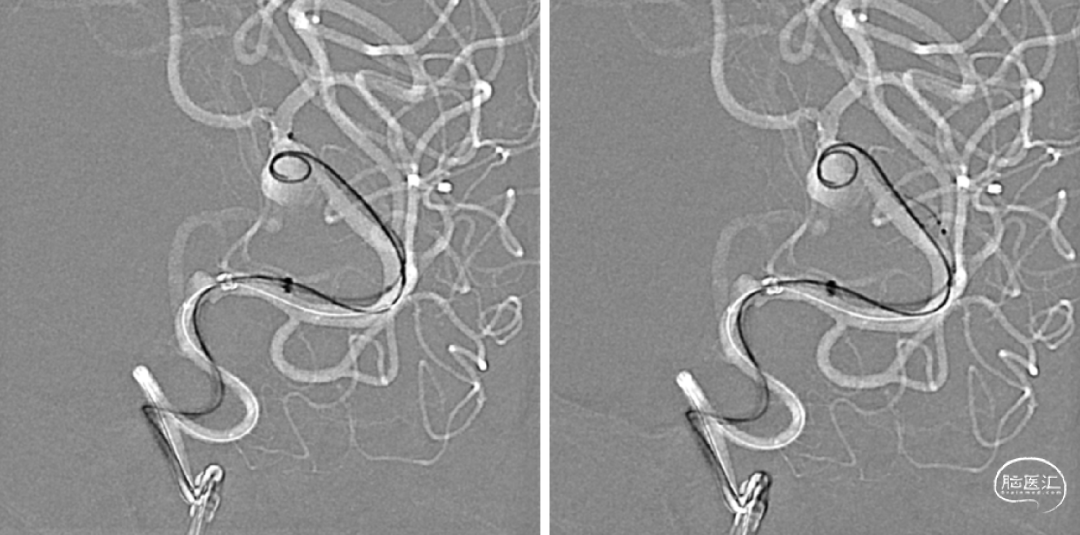

手术规划:FD+弹簧圈

FRED 3.0x14/19